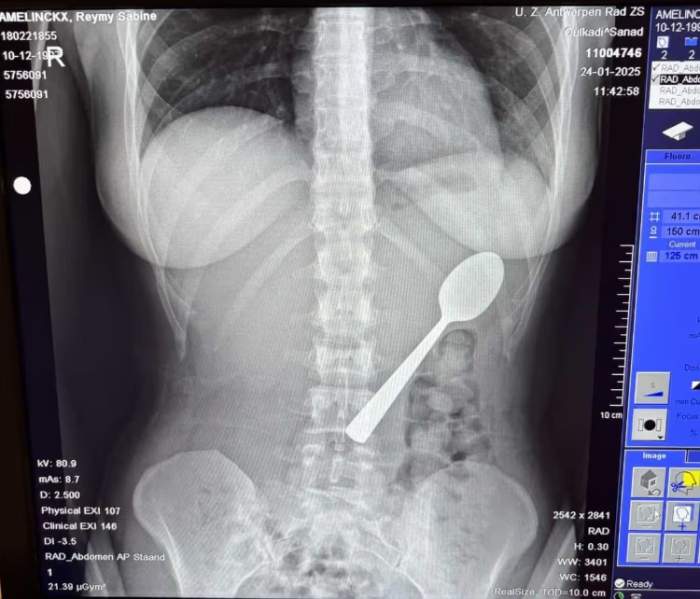

O femeie a înghițit accidental o lingură lungă de 17 cm când câinele ei a sărit în poala ei în timp ce mânca iaurt. Reymy Amelinckx a spus că a trebuit să aleagă între „a se sufoca sau a înghiți lingura”, deoarece a simțit cum tacâmul „aluneca ușor în stomac”.

O femeie a înghițit din greșeală o lingură lungă de 17 cm

Tânăra în vârstă de 28 de ani a povestit că stătea pe canapea și mânca iaurt în momentul în care câinele ei, un vizsla maghiar, pe nume Marley, a sărit brusc pe ea.

Femeia povestește că a încercat inițial să scoată lingura de 17 cm cu mâna.

Tinerei i-au scos lingura din stomac două zile mai târziu

Ustensila i-a fost îndepărtată sub anestezie locală, fără să fie nevoie de o intervenție chirurgicală deschisă.